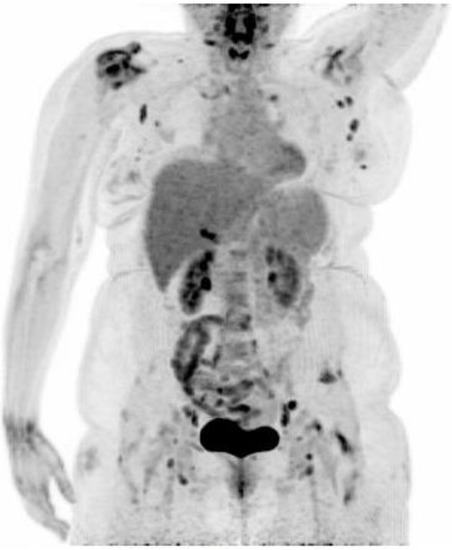

18F-FDG PET/CT Findings in a Patient with Chikungunya Virus Infection